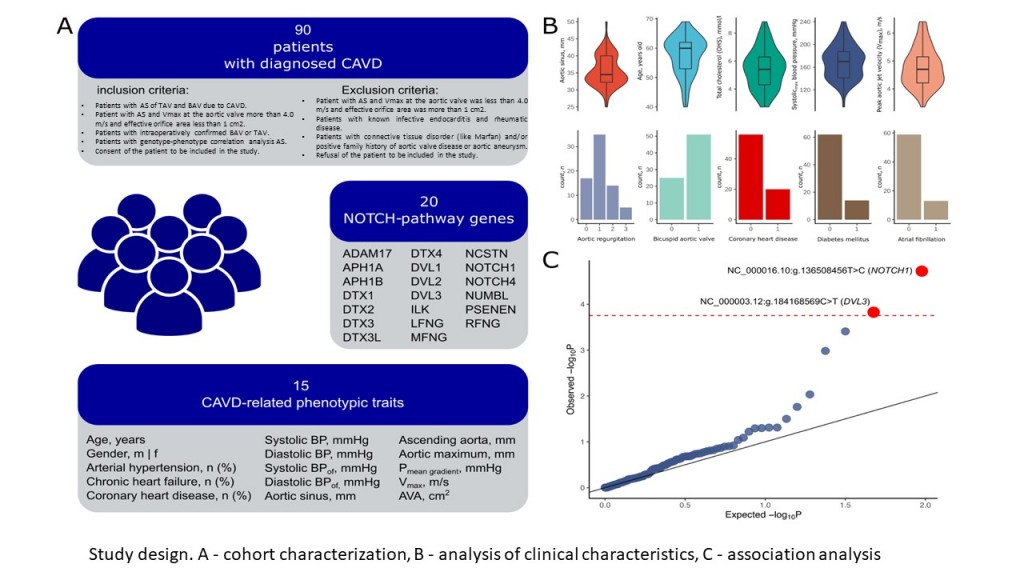

Irtyuga, O. The Role of NOTCH Pathway Genes in the Inherited Susceptibility to Aortic Stenosis / Irtyuga O., Skitchenko R., Babakekhyan M., Usoltsev D., Tarnovskaya S., Malashicheva A., Fomicheva Y., Rotar O., Moiseeva O., Shadrina U., Artomov M., Kostareva A., Shlyakhto E. // Journal of Cardiovascular Development and Disease. – 2024. – Vol. 11. – №. 7. – P. 226

Irtyuga, O. NOTCH1 mutations in aortic stenosis association with osteoprotegerin/RANK/RANKL / Irtyuga O., Malashicheva A., Zhiduleva E. [et al.] // BioMed research international. – 2017. – Vol. 2017. – P.6917907.